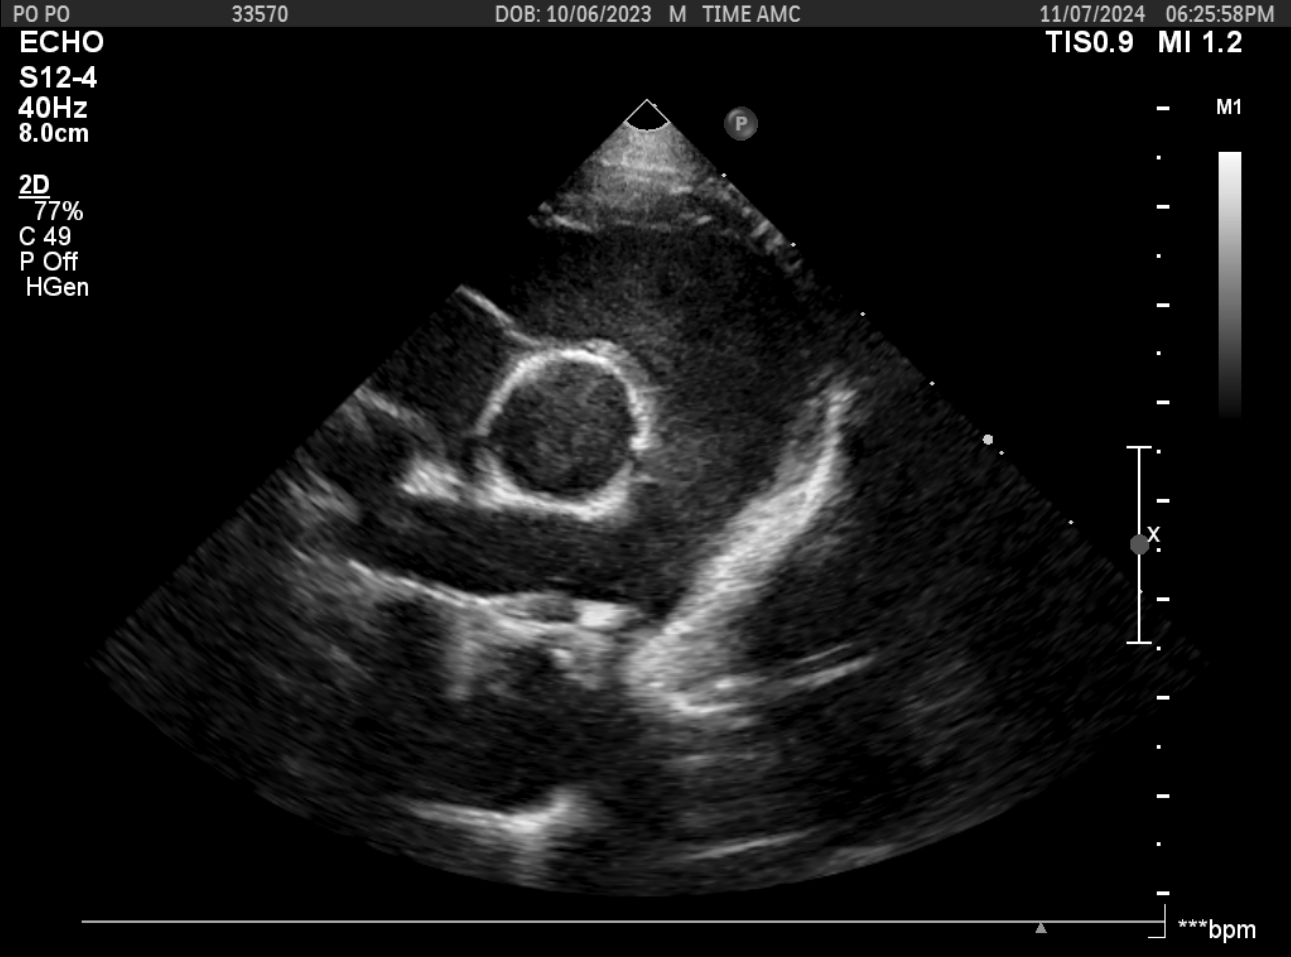

PDA 교정 시술 전후 초음파 비교

시술 전 1

시술 전 2

PDA 교정 시술 전후의 초음파 비교입니다. 시술 전에는 동맥관 개존증으로 인한 비정상적인 혈류 패턴이 도플러 초음파로 확인되며, 시술 후에는 PDA plug 삽입으로 정상적인 혈류 패턴으로 회복된 상태를 보여줍니다.